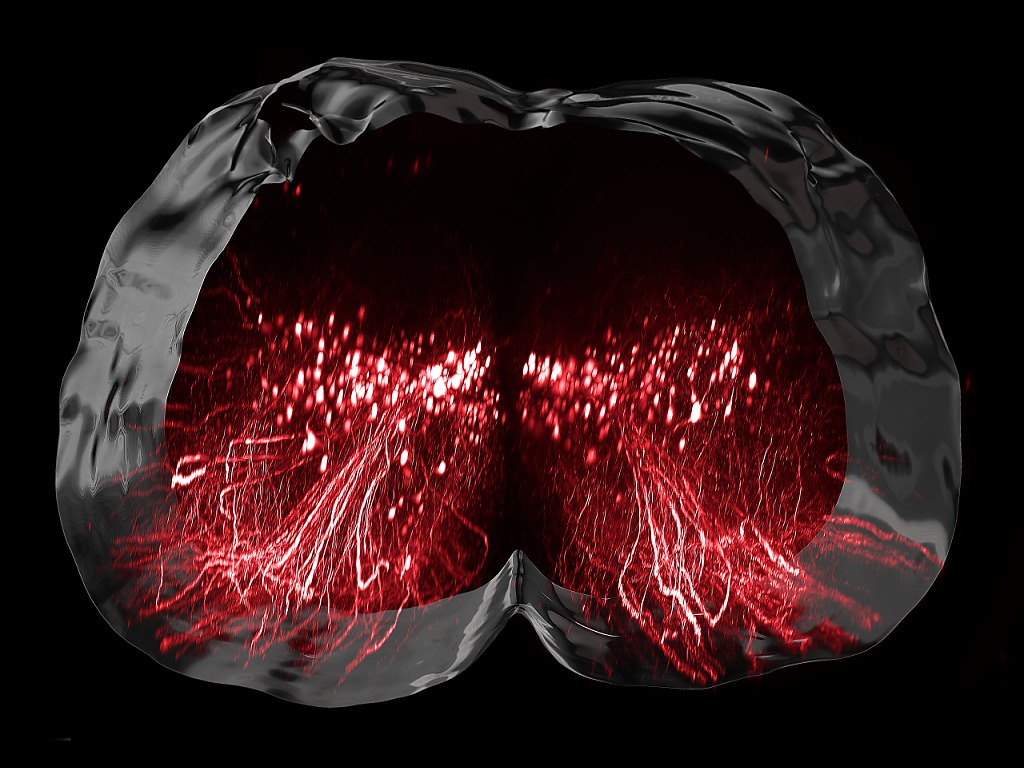

Les scientifiques ont donc étudié cette récupération sur un modèle de rongeurs. Cela leur a permis d’identifier une famille de neurones qui ne sont pas particulièrement sollicités pour la marche des individus en bonne santé, mais qui se révèlent essentiels pour la récupération après une lésion de la moelle épinière.

"Nous avons pour la première fois pu établir un atlas moléculaire de la moelle épinière d’une précision telle qu’il nous permet d’observer, neurone par neurone, l’évolution du processus de guérison", souligne Grégoire Courtine, professeur de neurosciences à l’EPFL et co-directeur du centre .NeuroRestore, cité dans le communiqué.

Les chercheurs ont ainsi montré que la stimulation de la moelle épinière active un type de neurones spécifiques appelé Vsx2, et que l’importance de ces neurones croît avec le processus de récupération.